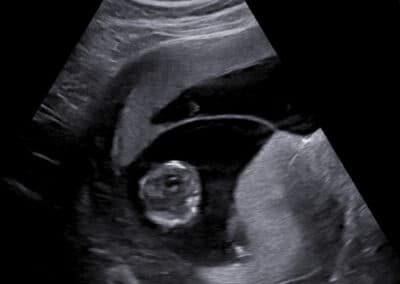

Vyšetření počtu placent, tzn. chorionicity –monochoriální biamniální dvojčetné (jednovaječné) těhotenství, které je více rizikové ohledně výskytu komplikací

Vyšetření počtu placent, tzn. chorionicity –bichoriální biamniální dvojčetné (dvoj-, ale může být, i když méně často, jedno-vaječné) těhotenství, které je méně rizikové ohledně výskytu komplikací